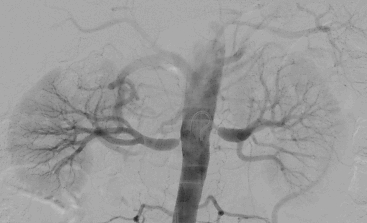

Renal captopril scintigraphy is not recommended in relevant guidelines. In any case, the gold-standard is formal invasive angiography. We confirm stenosis visually and by using trans-lesion pressure gradient measurements.

Atherosclerotic renal artery disease does not only have different imaging characteristics than fibromuscular dysplasia of the renal arteries, but also appears in different types of populations. Atherosclerotic renal artery disease is most often in the ostium of the renal artery and is a single lesion, while fibromuscular dysplasia tends to be distal and demonstrate beading. Also, fibromuscular dysplasia is more common in young women, atherosclerosis is more common in the elderly.

- During the procedure the operator must make sure that there is a significant pressure gradient across the lesion (more than 20 mmHg). Also, the fractional flow reserve, renal frame count and renal blush grades may offer useful information. A procedure should not proceed to stenting if these factors do not align favorably. Criticism of most of the negative trials that found that renal artery stenting was ineffective is that intra-procedural measurements were lacking.